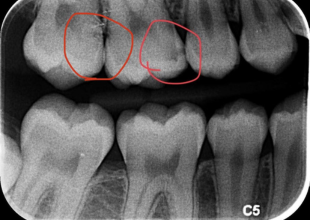

Computerized X-Ray, also known as digital radiography, is an advanced imaging technology used in modern dentistry to capture highly detailed images of your teeth, gums, and jaw. Unlike traditional X-rays, this system uses significantly lower radiation while providing faster and clearer results. The digital images help dentists diagnose problems accurately and plan effective treatments with greater precision.

- Early detection of cavities and tooth decay

- Identifying infections or abscesses